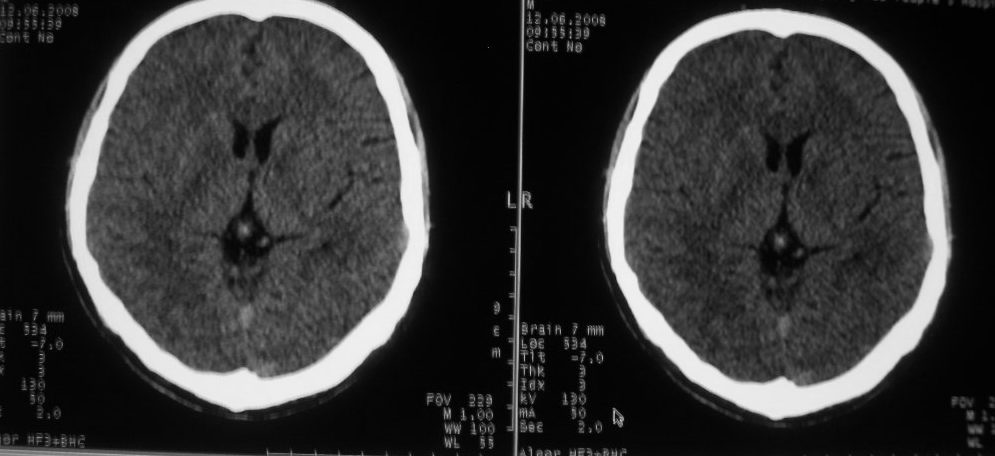

以下是引用守望可可西里在2008-6-13 1:25:00的发言:[br][br] 1.双侧大脑中动脉高密度踌型样接近于全程显示,部分大脑前动脉、基底动脉也呈高密度改变。[br] 2.右侧基底节多发类圆形ct值接近于出血的高密度,边缘模糊。双侧小脑幕及直窦、上矢状窦增宽、模糊。左侧横窦和乙状窦区密度增高、呈云雾状,内缘模糊。[br] 如果这样的表现发生在一个老年人脑部,我们首先会想到是高血压、动脉粥样硬化,就可以很容易得出结论。但这发生在一个20岁年青人的身上,且病程长达半年、临床症状不怎么重,这就比较蹊跷且应该引起高度重视了。[br] 我认为此病人应该是一个血液病患者--双侧大脑中动脉、部分大脑前动脉及基底动脉的高密度改变,只是一个假象:即相对于ct值偏低,只有35的脑灰质而言的相对高密度。而那么多出血改变,则是真正的病变表现。[br] 建议临床进一步进行其他相关的血液、骨髓检查,肝、脾也应该好好检查,应有明显的肿大。